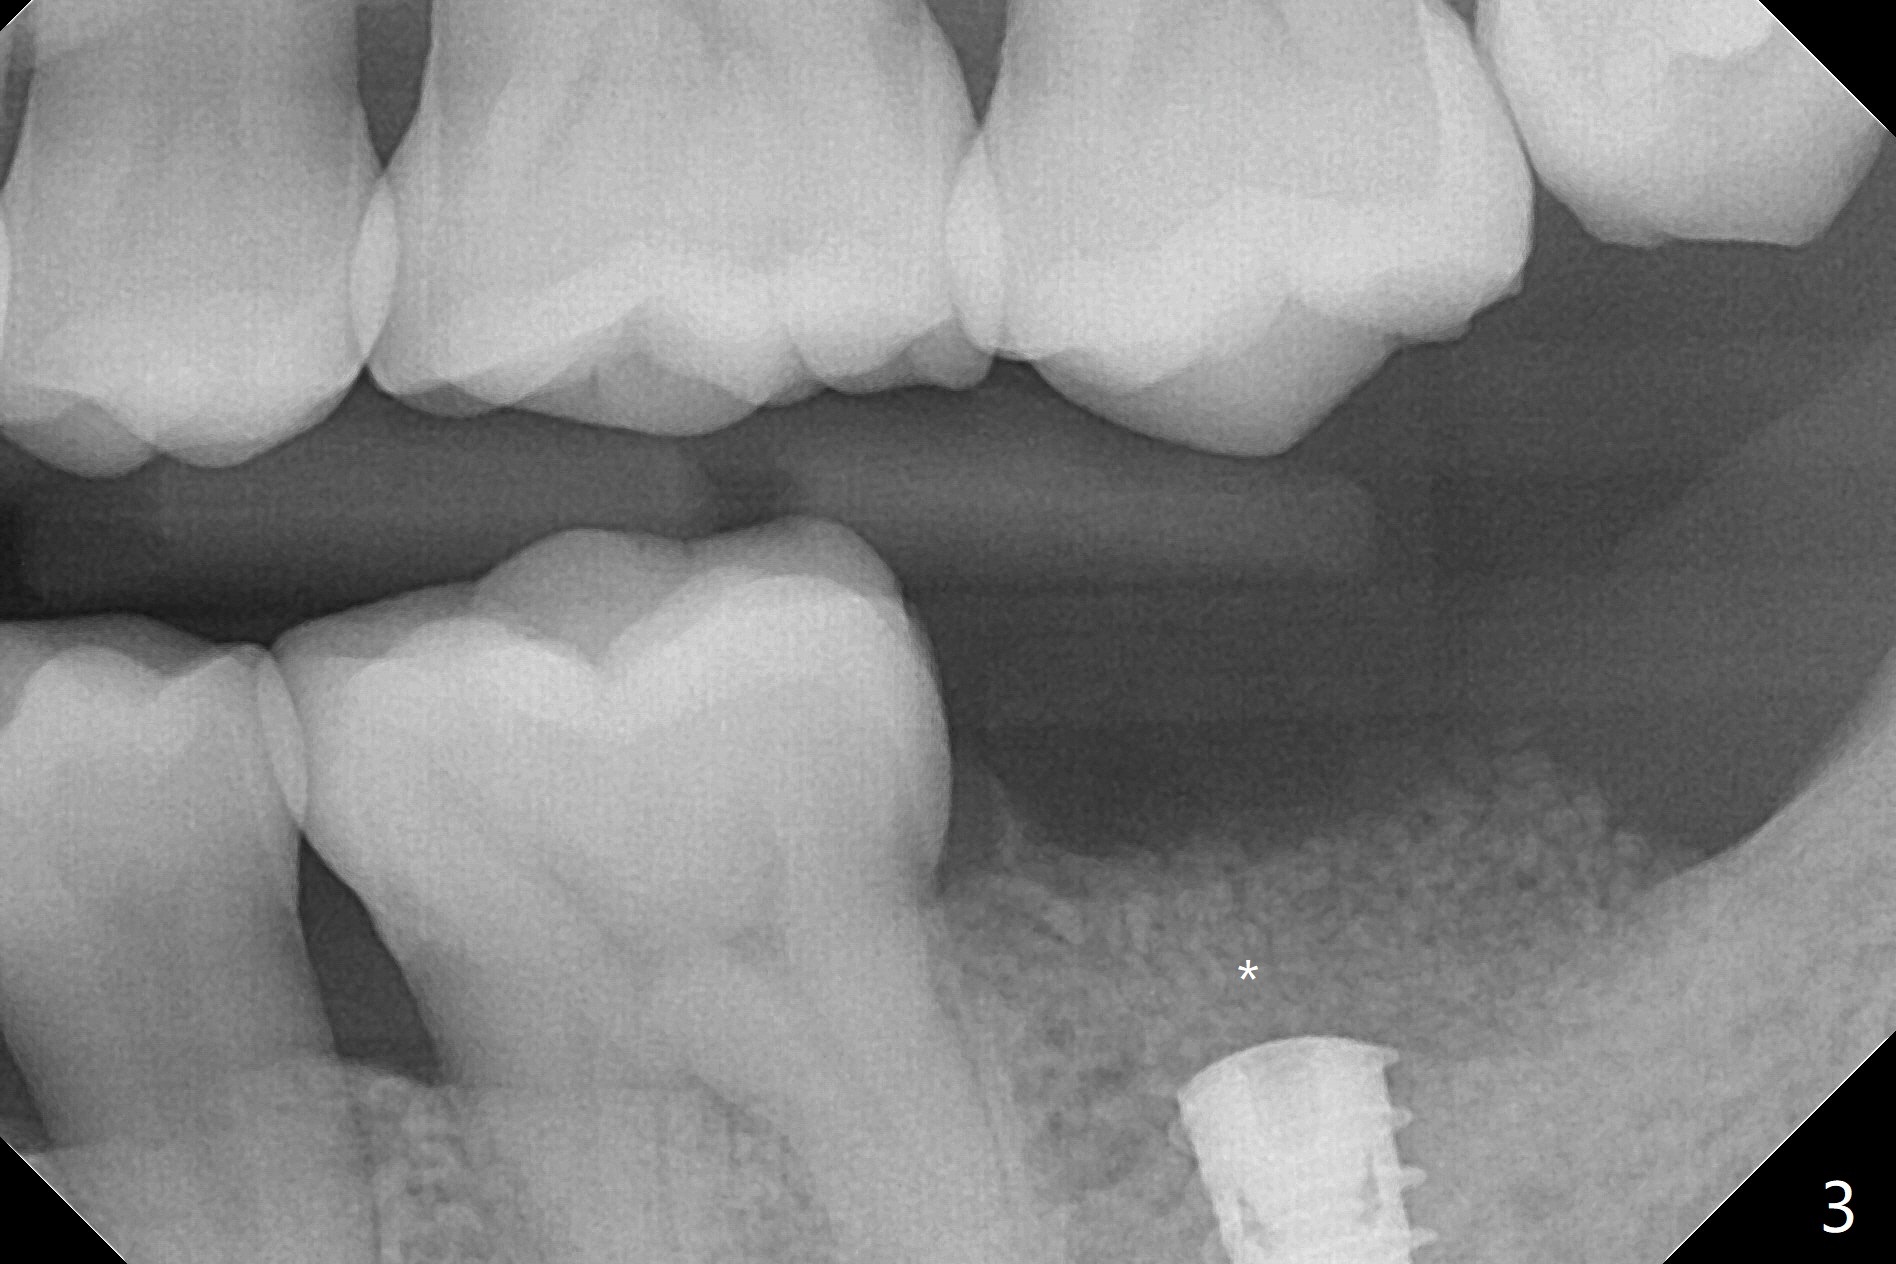

左下7钻洞中出现三种情况:容易出血(血小板减低(9万)),疼痛(根尖肉芽肿)和骨质疏松,钻洞深度还没达到,使用短小报废植体拍摄根尖片(图一),之后下颌牙槽神经阻断,钻洞没有疼痛,但是未注意骨质疏松问题,按照正常钻洞顺序,所以正式植体扭力低,10 Ncm(图二),放置骨粉和不可吸收膜,PTFE缝合(图三)。术后一周膜舌侧稍微外翻(剪太小些,图四)。病人将术后五周回来去除膜,之后拍摄咬翼片证实骨粉丧失与否。其实病人提前回来,抱怨缝线不适,膜不翼而飞(图五,折线后),患侧咀嚼,因为对侧下颌第二磨牙疼痛又不肯拔除。The bone graft placed at the time of immediate implant (Fig.3 *) is apparently changing into the normal bone 4 months postop before uncover (Fig.6). After removal of the bone coronal to the implant with a curette, a 4x4(3) mm pair abutment is placed (Fig.7). Two weeks later the abutment screw is torqued at 20 Ncm.